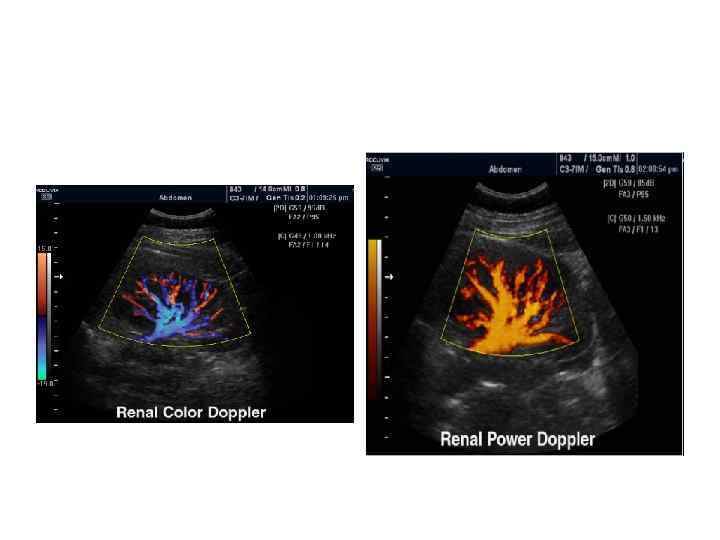

УЗИ сосудов почек

Цветовой допплер (Color Doppler) Кровоток • к датчику принято картировать красным цветом, • от датчика - синим цветом. • Турбулентный кровоток картируется сине-зелено-желтым цветом.

Энергетический допплер (Power Doppler). • Применяется для регистрации низкоскоростного кровотока. • При использовании энергетического допплера теряется направление кровотока. • В настоящее время энергетический допплер используют в сочетании с контрастными веществами (левовист и др. ).

Энергетический допплер - power doppler